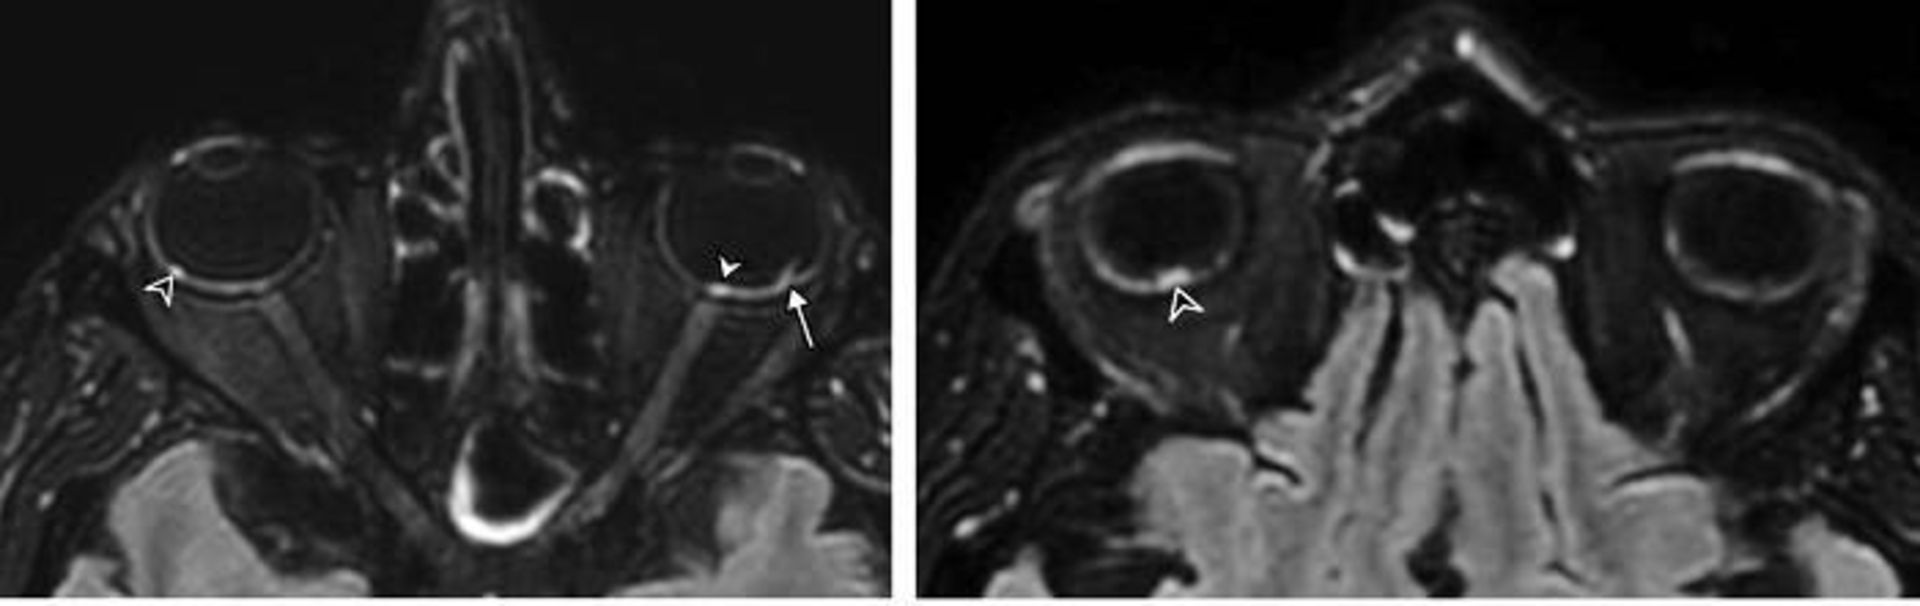

اسکن بیمار کووید /  covid patient scan

مطالعه‌ی جدیدی نشانه‌هایی از ناهنجاری‌های چشمی را روی اسکن‌های MRI بیماران مبتلا به کووید ۱۹ شدید نشان داد. در بالا، اسکن‌های MRI مغز بیمار ۵۶ ساله‌ی مبتلا به کووید ۱۹ ندول‌هایی را در پشت چشمان وی نشان می‌دهد (که با پیکان نشان داده شده است) که می‌تواند نشانه‌ای از التهاب یا آسیب مستقیم به چشم باشد.